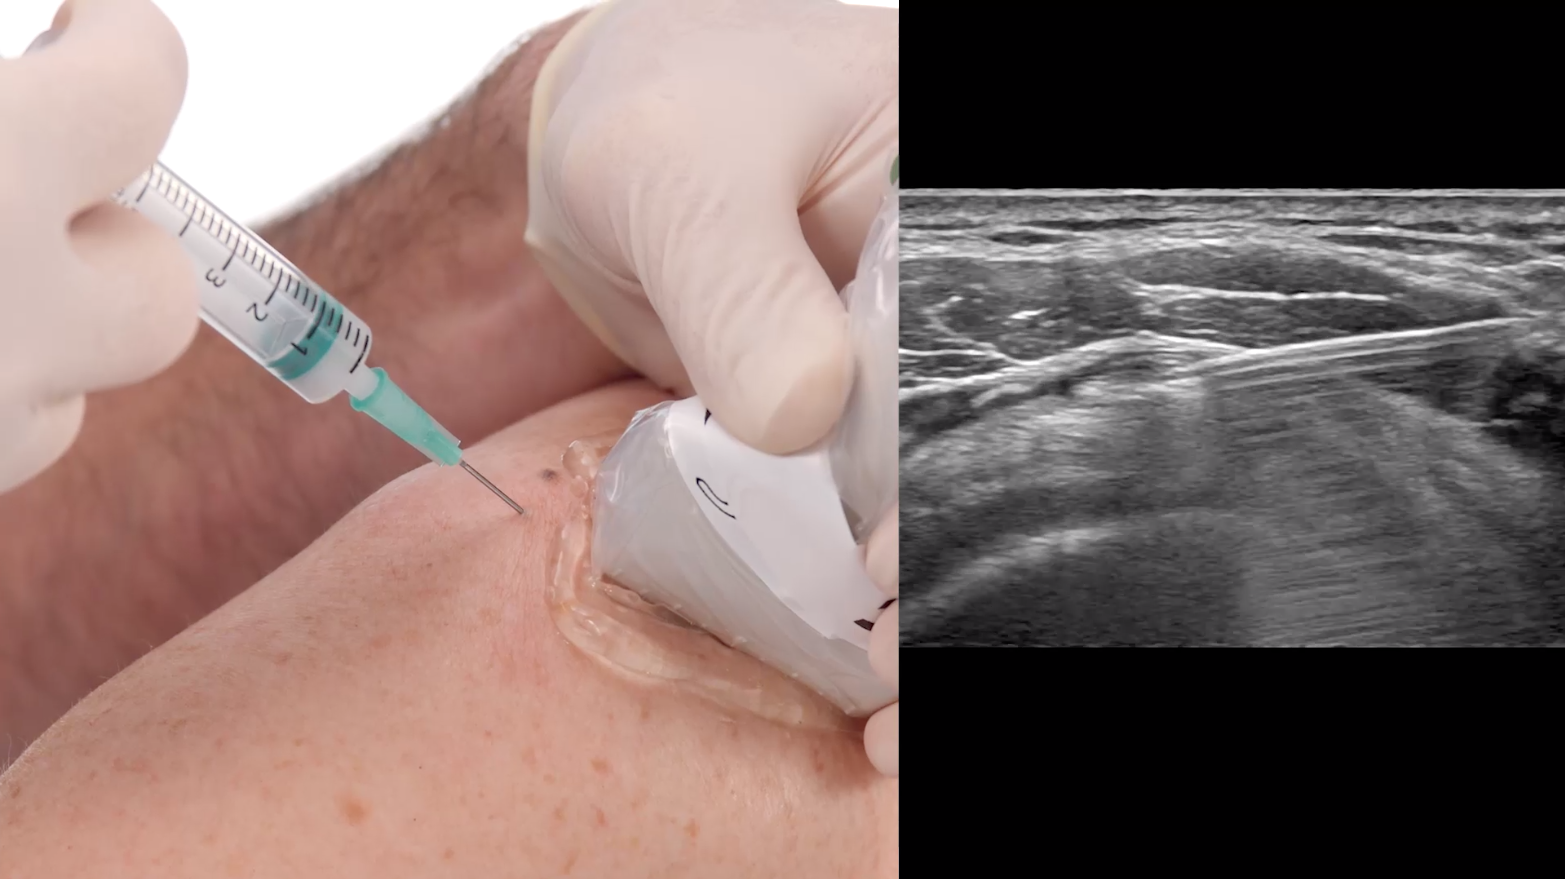

Υπερηχολογικά καθοδηγούμενες εγχύσεις

Είναι πολύ σημαντικό οι εγχύσεις που πραγματοποιούνται στο ιατρείο να γίνονται όσο το δυνατό περισσότερο στοχευμένες γιατί αυτό αυξάνει σημαντικά την πιθανότητα της θεραπείας. Οι εγχύσεις τις οποίες πραγματοποιούμε υπερηχολογικά είναι:

Πλεονεκτήματα των καθοδηγούμενων εγχύσεων με υπέρηχο:

- Ακρίβεια στη στόχευση της περιοχής ενδιαφέροντος χωρίς να κακοποιούνται οι παρακείμενοι ιστοί.

- Πολλαπλάσιες πιθανότητες επιτυχίας της θεραπείας

- Λιγότερος πόνος

- Αποφυγή αιματωμάτων και τραυματισμών άλλων δομών